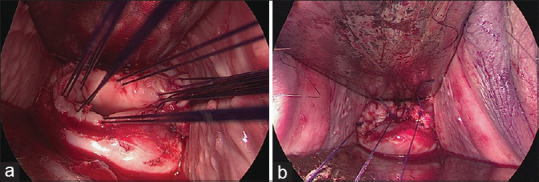

Materials and methods: We retrospectively analyzed data from 103 patients with cervical cancer who underwent radical hysterectomy at Kagoshima University Hospital between 2007 and 2023. The patients were divided into the LRH with SNNS and open surgery groups. All LRH procedures involved closing the vagina using a vaginal cuff without a uterine manipulator. Clinicopathological factors and oncological outcomes, including 5-year recurrence-free survival (RFS) and overall survival (OS), were compared between the groups.

Results: The 5-year RFS and OS rates were 92.7% and 94% and 85.5% and 88.3% for LRH and open surgery, respectively, with no significant intergroup differences. No peritoneal dissemination or recurrence was observed in the LRH group. LRH with SNNS procedure achieved 100% sentinel node identification, and lower extremity lymphedema or pelvic lymphocele did not occur.

Conclusion: LRH with SNNS and open surgery for cervical cancer exhibited comparable long-term outcomes. Vaginal closure using a vaginal cuff without a uterine manipulator is crucial for preventing cancer spillage. Combining LRH with SNNS is less invasive and avoids compromising oncological outcomes. High-quality randomized controlled trials are required to validate these findings.